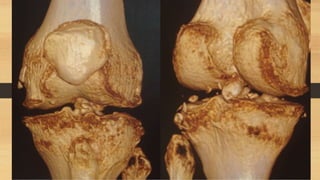

CLASIFICACIONES

Schatzker

Khan